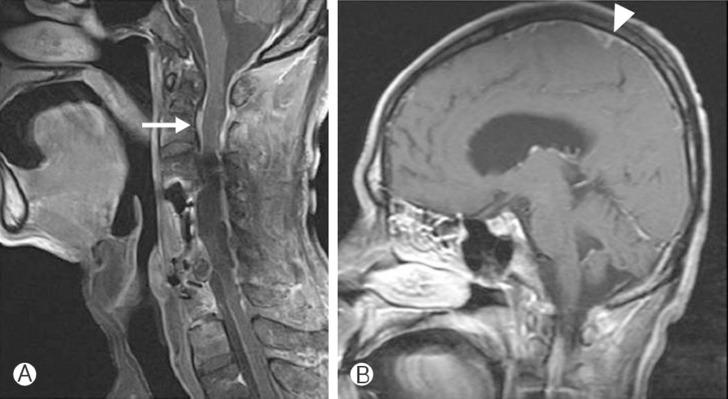

We report two cases of cervical spinal epidural abscess (SEA), which are related to anterior cervical surgeries. The first case reveals a late postoperative infection without any predisposing factor. The second case reveals combined complication of infection and instrument failure (artificial disc). Both two cases manifested ascending infections that are unusual courses of anterior cervical infections. The abscess extended upwards and, finally, caused life threatening bacterial meningitis. We suggest aggressive surgical interventions with anti-bacterial therapies in such cases.

我们报告了两例与颈椎前路手术相关的颈椎硬膜外脓肿(SEA)病例。第一例显示为术后晚期感染,无任何诱发因素。第二例显示为感染与器械故障(人工椎间盘)的合并并发症。两例均表现为上行性感染,这是颈椎前路感染的不寻常病程。脓肿向上蔓延,最终导致危及生命的细菌性脑膜炎。我们建议在此类病例中采取积极的手术干预并联合抗菌治疗。